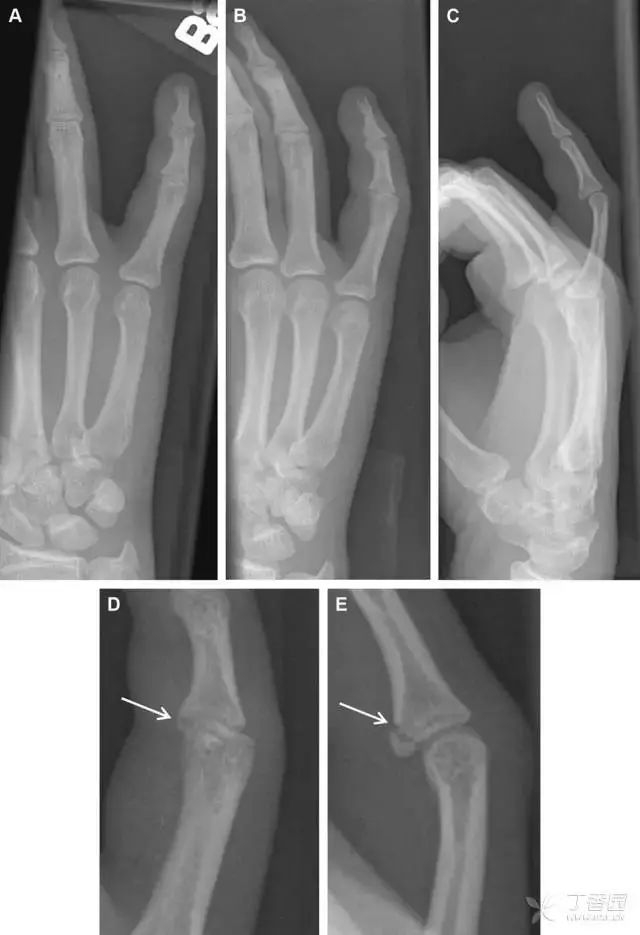

32掌板骨折

掌板是掌指关节和指间关节关节囊掌侧的纤维结构,防止关节过伸。掌板的远端部是增厚的纤维软骨,附着于指骨掌侧基底部,而其两侧与侧副韧带的纤维融合。掌板骨折多发生于过伸损伤,为撕脱性骨折。

图 3 掌板骨折(A~C)小指前后位、斜位、侧位片,由于骨折的部位及特点,在前后位片上通常难以发现骨折;放大后的斜位(D)、侧位(E)可见一骨碎片(白色箭头)